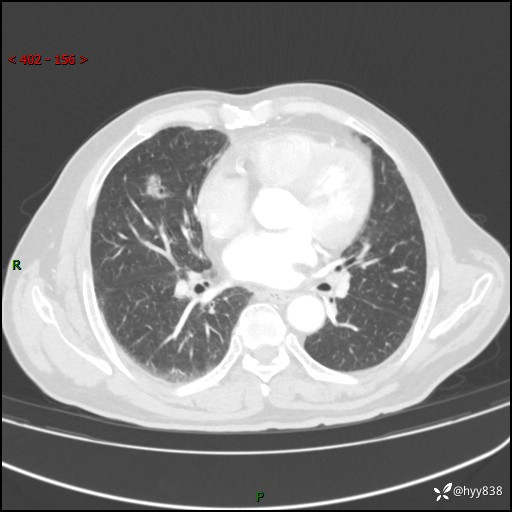

现病史:患者4月前无明显诱因后背正中间疼痛,间断阵痛,无低热、咳嗽,盗汗、咯血、胸痛、喘气等不适,2024-2-25当地市第二人民医院胸部CT提示“1.双肺感染病变;2.右肺中叶结节灶;3.双肺肺气肿并肺大泡4.主动脉及冠脉硬化,今为求明显结节性质遂来我院门诊就诊,门诊以“肺占位”收治入院。 起病以来,患者精神饮食睡眠一般,大小便正常,体力体重无明细变化。

胸部CT复查(2024.7)